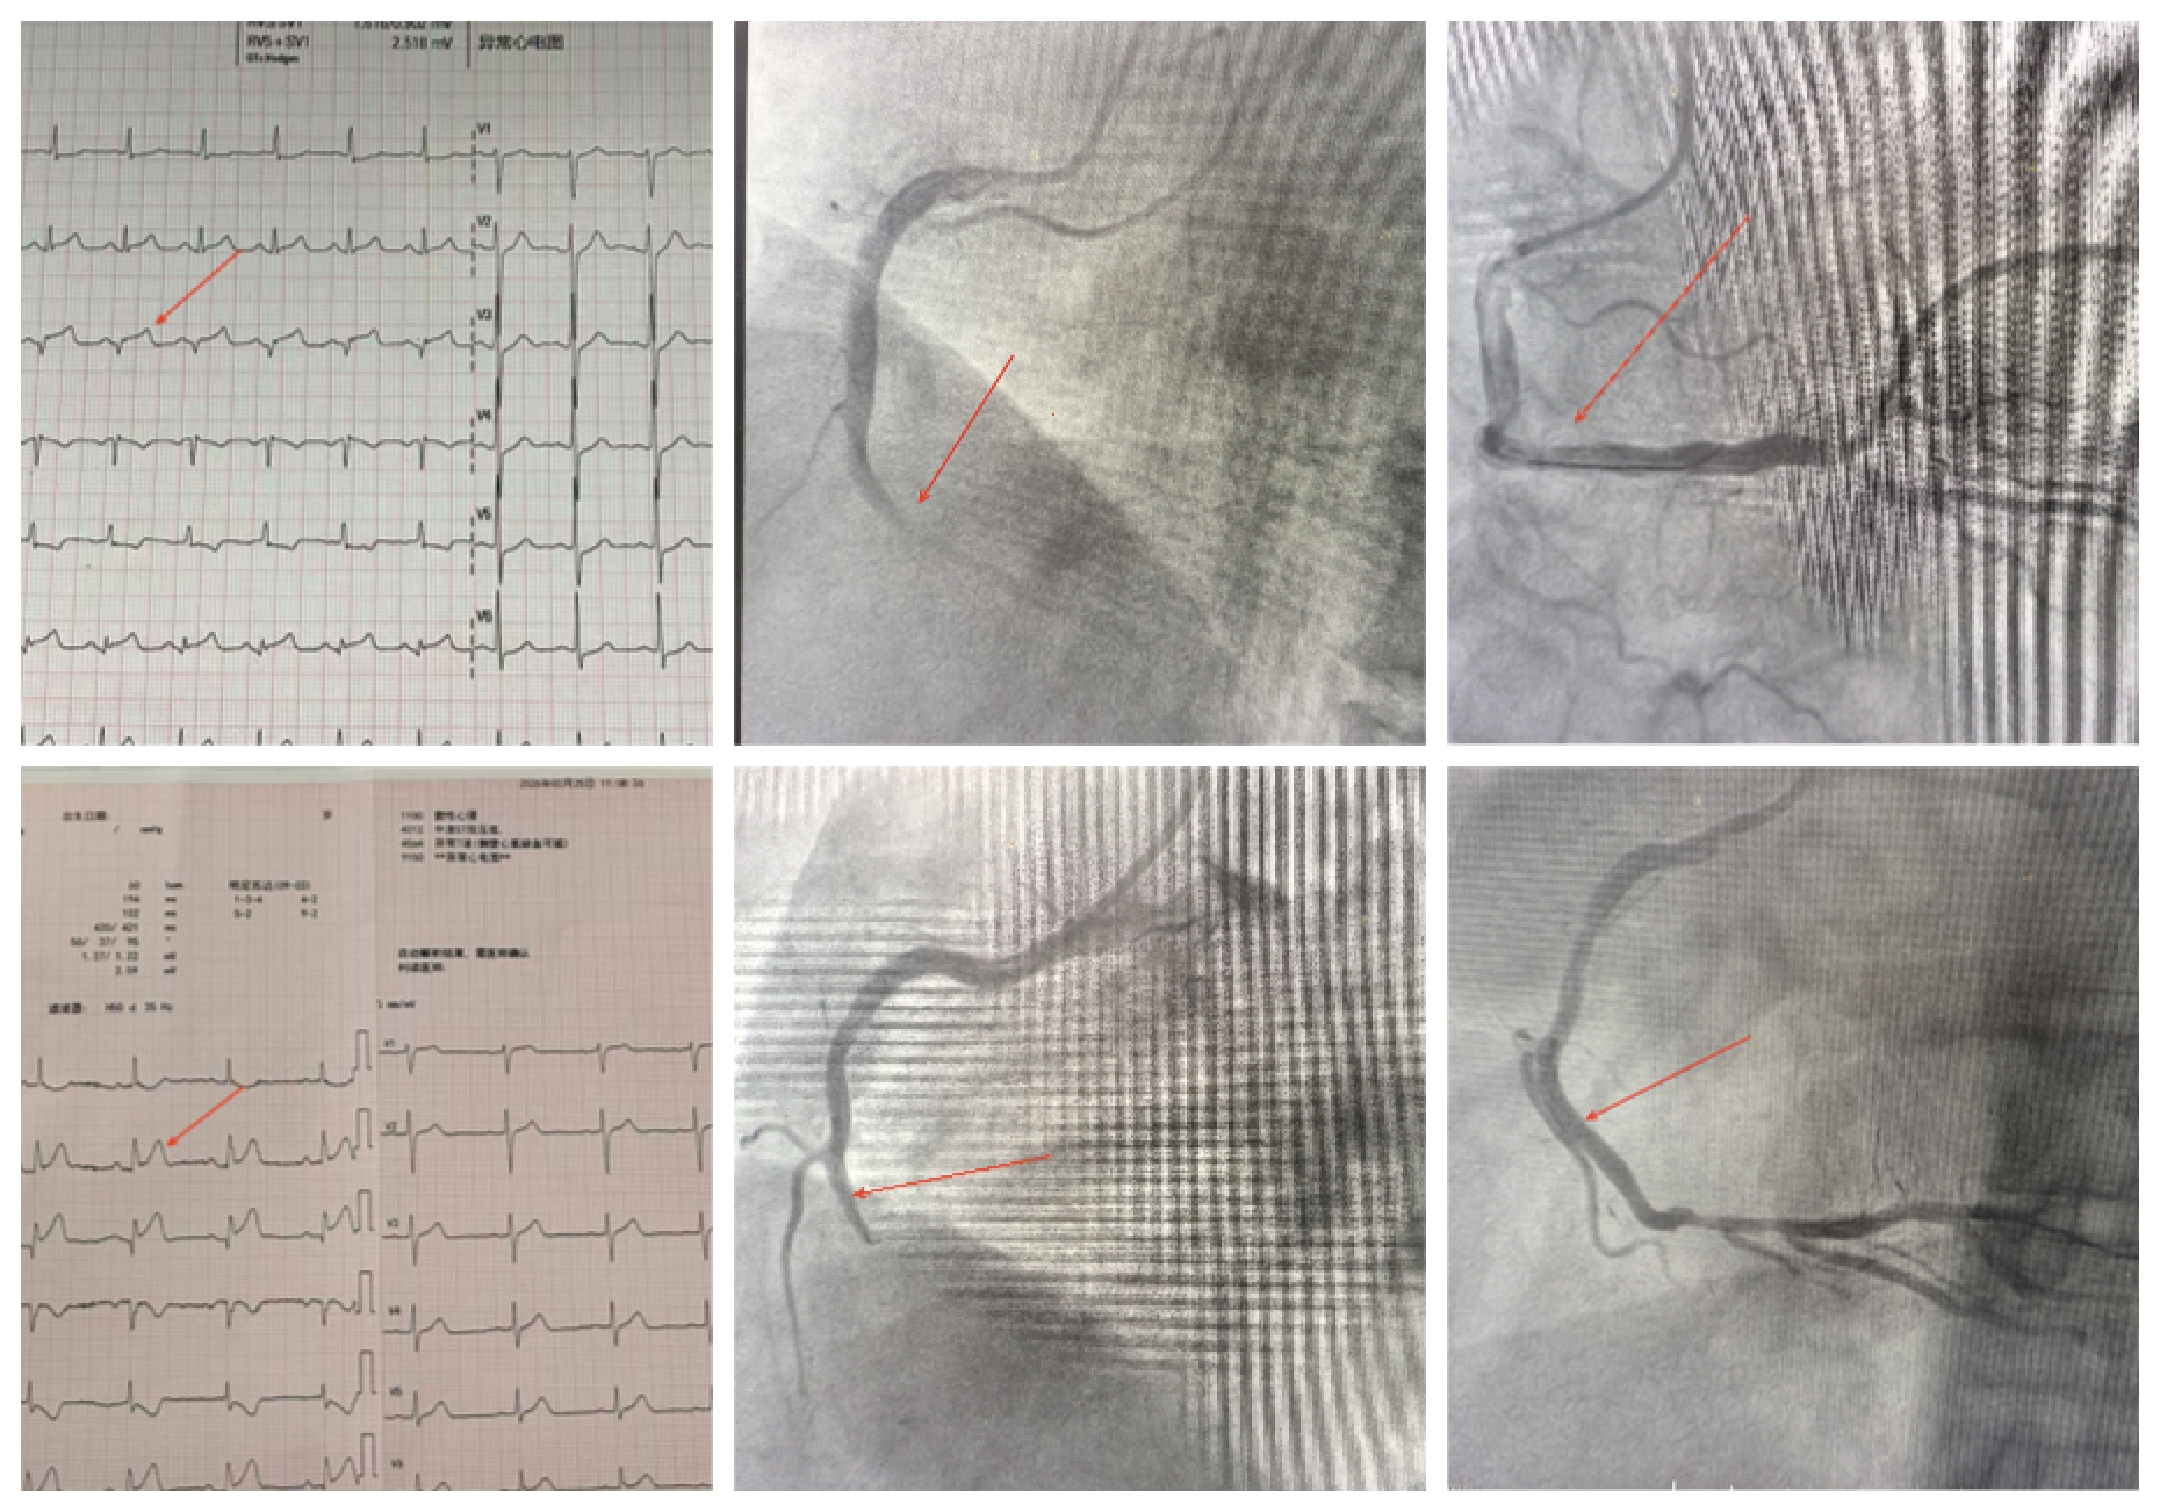

其中,38岁患者的救治过程尤为紧迫。该患者于凌晨02:00突发胸痛,呈压榨样剧痛,位于胸骨中下段后,范围约半拳大小,伴呼吸困难、大汗淋漓,症状持续约10分钟后缓解,但患者未及时就诊,直至清晨自行就诊。接诊医师高度警惕,立即安排检查,首份心电图显示:窦性心律,II、III、aVF导联ST段抬高,提示急性下壁心肌梗死。

时间就是生命,每一分每一秒都关乎患者安危。心血管科徐淑乐主任紧急赶到,查看患者后当即指示立即启动胸痛绿色通道,将患者紧急送往导管室实施介入手术。该患者就诊时无家属、同事陪同,病情紧急不容片刻耽误,医护人员经请示医务处,通过电话视频与患者家属取得联系,详细告知病情及手术风险,在征得家属同意后,为患者实施手术,术中出现多次危急情况,胸痛中心凭借丰富的临床经验与介入技术,沉着应对、精准操作,经过紧张有序的抢救,手术圆满成功,成功开通闭塞的冠状动脉,恢复心肌正常供血,患者胸痛症状缓解,生命体征逐渐平稳,安返CCU病房,目前病情稳定,正在进一步康复中。